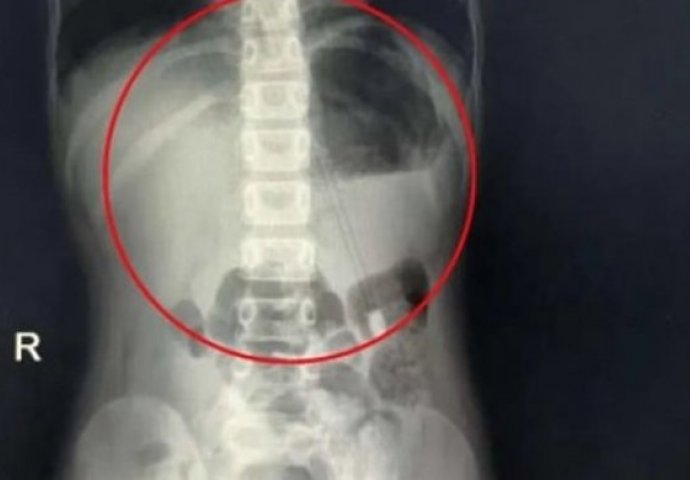

Dječaku iz Kine ljekari su izvadili iz stomaka olovku dugu 18 centimetara koju je progutao dok je radio domaći zadatak, piše Dejli mejl.

Rendgenski snimci pokazali su šiljati objekat duž djetetovog abdomena.

„Imao je sreće jer je oštar deo olovke bio na gornjoj strani. Da je bio okrenut nadole, vjerovatno bi mu olovka probušila želudac i druge dijelove digestivnog trakta“, objasnio je šef ljekarskog tima koji je u bolnici u Henanu bio zadužen za dječaka.